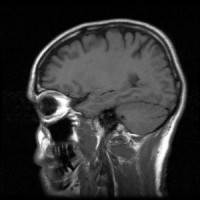

Az MR, MRI vizsgálat (mágneses rezonancia vizsgálat) fájdalommentes diagnosztikai módszer, amely a test anatómiai viszonyait tükröző, kitűnő térbeli és kontrasztfelbontású képet ad. A vizsgálat a következőket használja: egy erős mágnes, biztonságos, kis energiájú rádiósugarak valamint egy számítógép, amely a 2 vagy 3 dimenziós képet végül megalkotja.

mri-agy-d00000E8844bb9ec3a81b

Forrás: EgészségKalauz

A készülék megméri a test különböző pontjaiból jövő jelintenzitásokat, továbbítja a számítógépnek, amely ezt egy ún. szürkeségi skálán ábrázolja az általa kirajzolt képen. A beteg szövetek az egészségestől eltérő jeleket bocsátanak ki, a géppel ez detektálható. Az MRI keresztmetszeti ábrázolást tesz lehetővé tetszőleges síkokban.